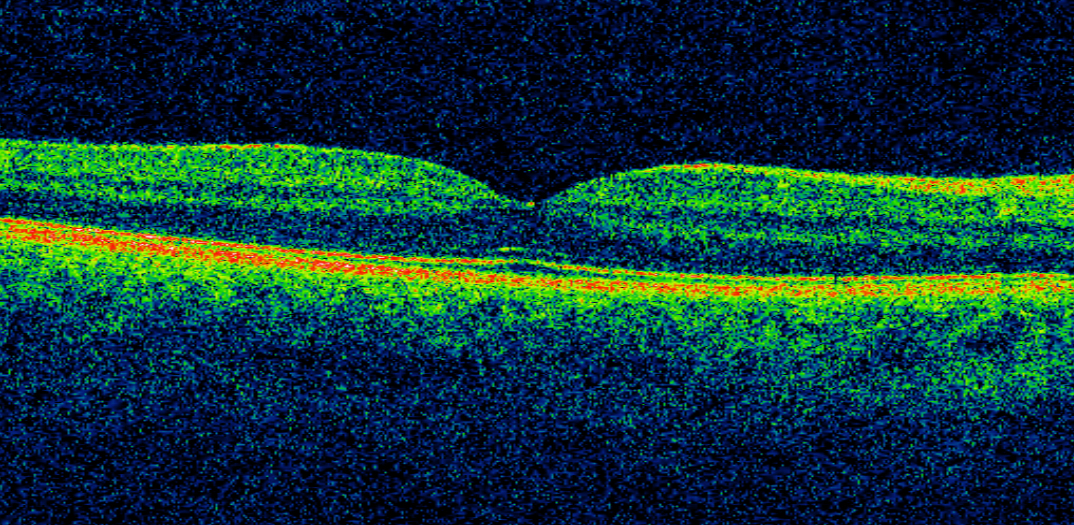

Foto: Una imagen de retina. Crédito: Moorfields Eye Hospital NHS Foundation Trust.

Cada semana, el Hospital Ocular Moorfields en Londres (Reino Unido) realiza 3.000 tomografías de coherencia óptica (TCO) para diagnosticar problemas de visión. Las TCO, que emplean luz de dispersión para generar imágenes de alta resolución en 3D de la retina, generan enormes cantidades de datos. Analizarlos es un proceso lento. Entender las imágenes depende de ojos humanos especializados y entrenados para identificar problemas específicos en cada caso, lo que impide que se dedique tiempo a analizar tendencias más amplias, a escala de la población general, que podrían facilitar la detección temprana.

El trabajo inicialmente se centrará en identificar cómo diagnosticar automáticamente problemas visuales causados por la diabetes y la degeneración macular asociada a la edad. Los diabéticos tienen un 25% más de probabilidades de sufrir algún tipo de pérdida de visión que las personas no diabéticas, y la degeneración macular representa la causa más común de ceguera en Reino Unido. En ambos casos, la detección temprana puede permitir un tratamiento más eficaz.